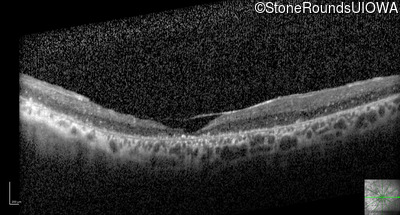

Optical Coherence Tomography - Left - 10/100 -2

Exemplar / OCT Stack